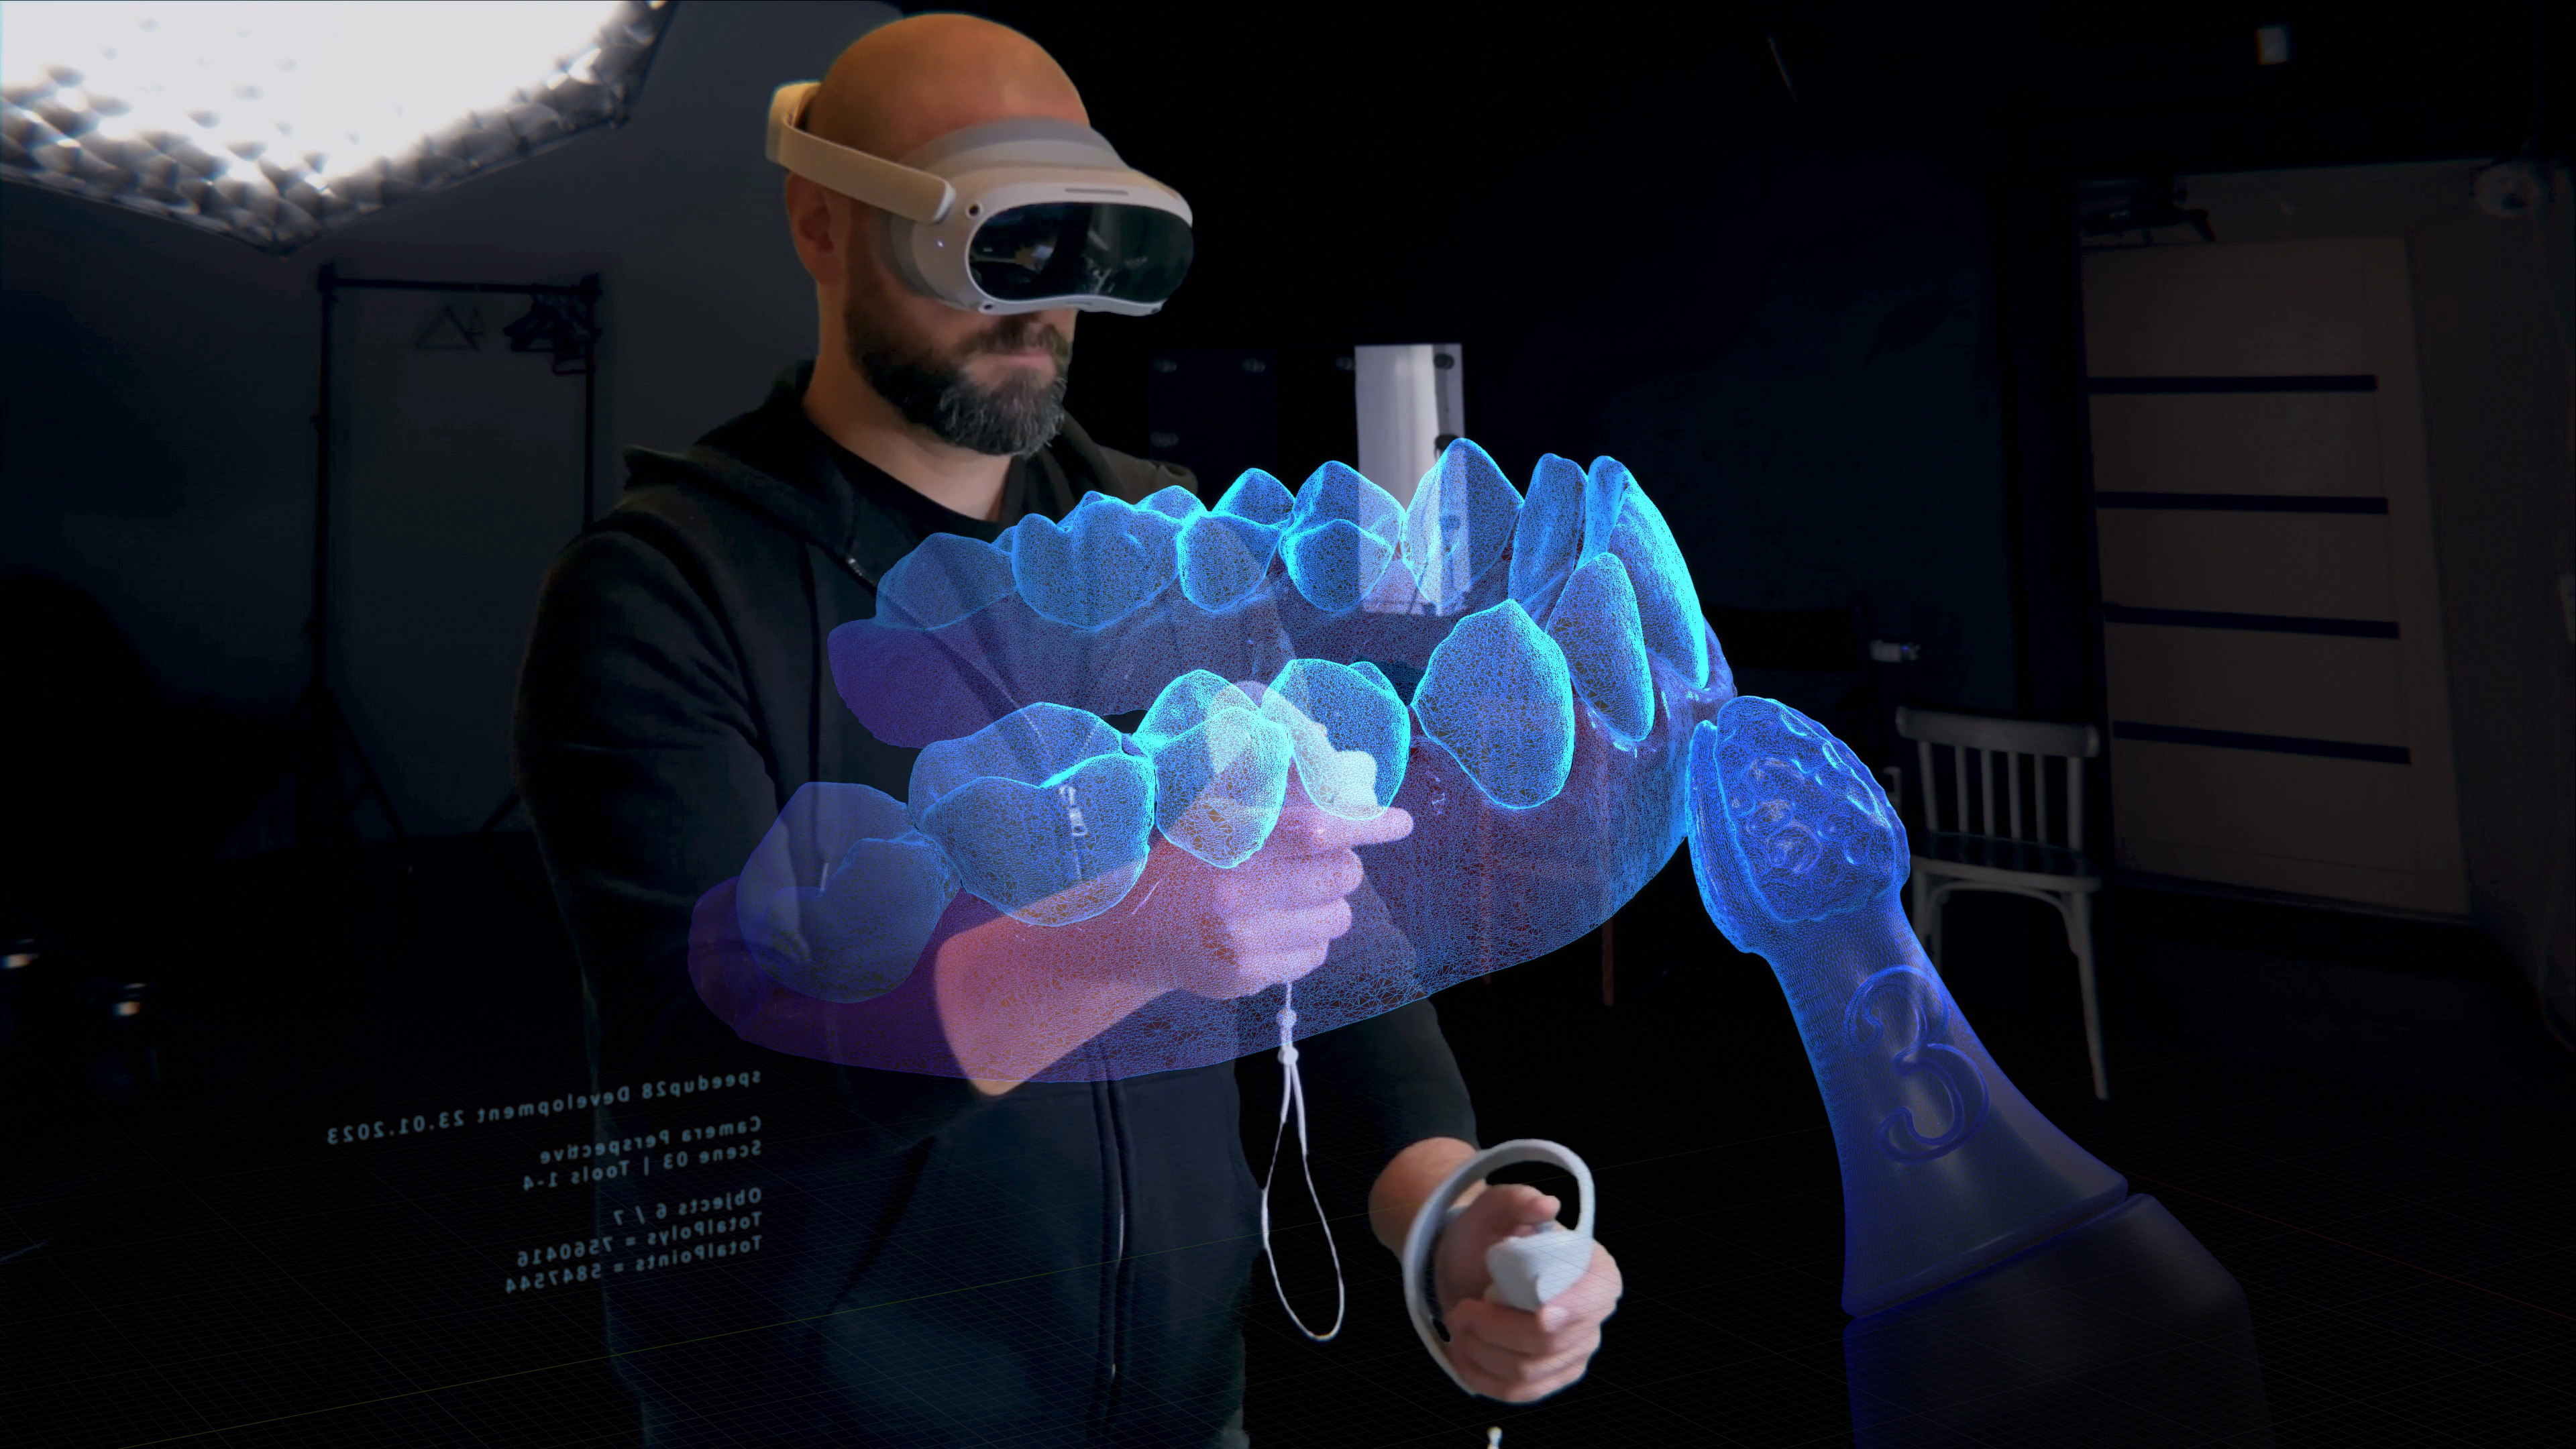

Oberflächenveredelung von Prothesenkörpern

Schnell, überzeugend und der Natur ein Stückchen näher. So kann man das Ergebnis beschreiben, dass mit speed up 28 erreicht wird.

Denn mit wenigen Handgriffen wird die Oberflächengestaltung von Prothesenkörpern natürlicher als jemals zuvor.

Besonderheit: Hochglanzpolitur mit hohem Detailreichtum möglich.